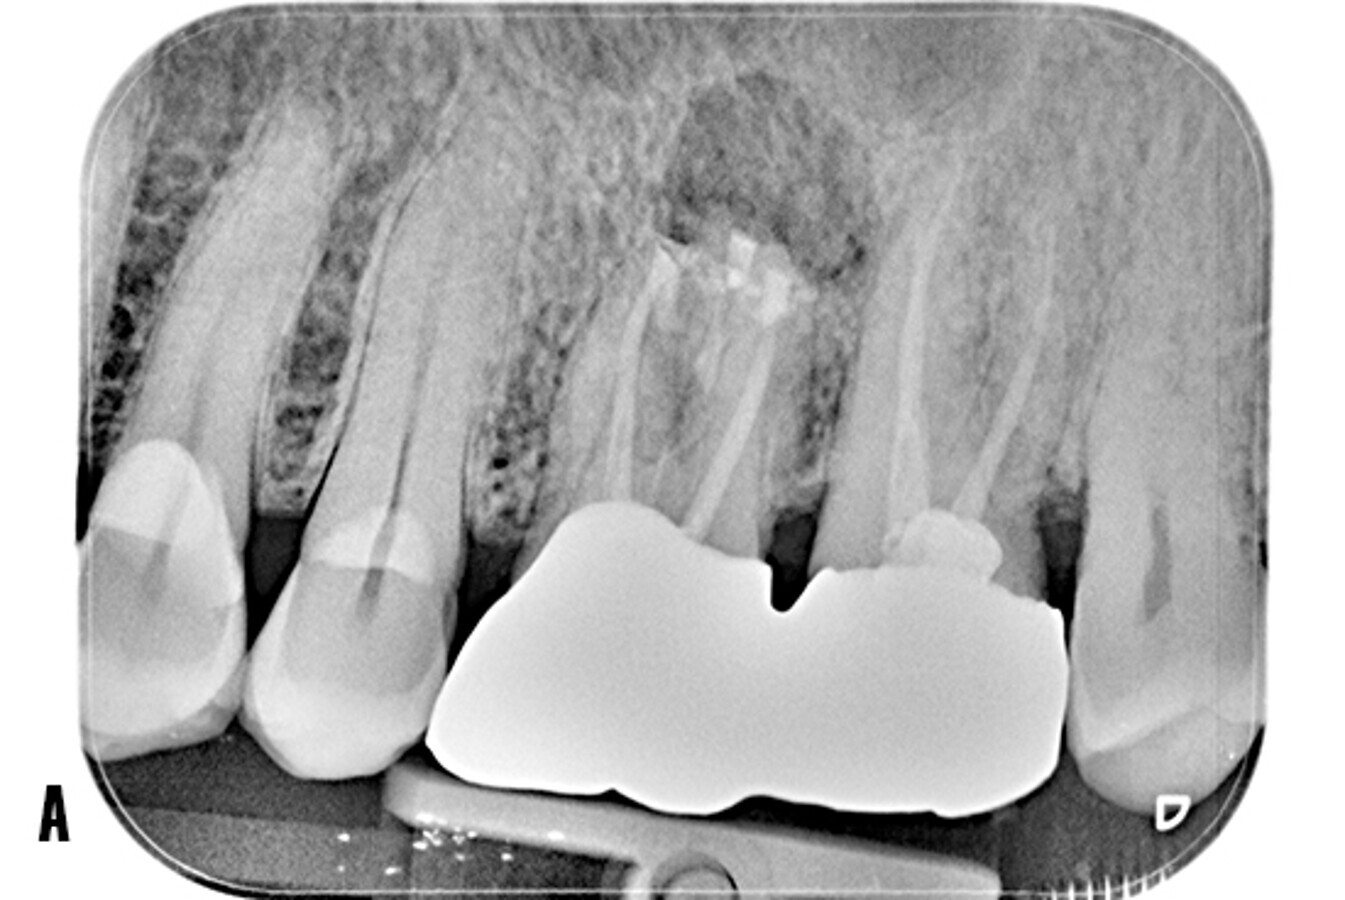

Tras realizar la evaluación radiológica bidimensional, en la ortopantomografía se observa los dientes 2.6 y 2.7 endodonciados y ferulizados mediante prótesis fija cementada (Fig. 2A). La radiografía periapical no evidencia una radiotransparencia bien definida a nivel apical. Las crestas alveolares interproximales se observan íntegras con bordes corticalizados bien definidos (Fig. 2B).

Figura 2. Evaluación radiológica bidimensional. A) La ortopantomografía advierte el tratamiento de conductos a nivel 26 y 27, portadores de prótesis fija metal-cerámica. B) La radiografía periapical muestra los dientes 26 y 27 endodonciados, se observa una imagen radiotransparente poco definida en apical de 26.

La TCHC muestra una imagen osteolítica menos radiodensa que afecta la región apical de 2.6, esta lesión compatible con un proceso osteolítico, es visible en los planos axial, coronal y sagital. Además, se observa cómo el seno maxilar izquierdo, relacionado al diente afectado, se torna más radiodenso y totalmente ocupado (Fig. 3).

Figura 3. Tomografía de haz cónico. A) Corte en el plano axial: se puede observar un área poco radiodensa en la raíz palatina de 26, y advierte la presencia de un proceso osteolítico de origen endodóntico. B) Corte coronal: se observa cómo el patrón de la lesión se extiende en sentido vestíbulo-palatino, además, se aprecia la cavidad sinusal anexa al diente afecto muy radiodensa respecto a su par contralateral. D) Corte sagital: se aprecia la opacificación completa del seno maxilar, la presencia de una septo óseo. La lesión apical tiene una mayor dimensión en la raíz palatina de 26.